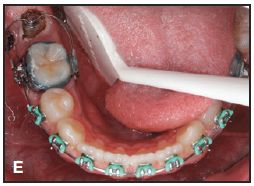

After surgical exposure of the impacted second molar with electrosurgery, a button is bonded to the occlusal surface. A U-loop is bent from .018" beta titanium wire and engaged between the buccal auxiliary tube and a lingually welded tube on the adjacent first molar. When placed passively in the tube, the loop should lie 2-3mm distal to the button (A). The center of the U is bent so that the wire will engage the button without displacement once the loop is activated (B). Crimpable stops are placed on the wire distal to the molar tube to prevent the loop from sliding after activation.

This technique is demonstrated in a 13-year-old female patient with an impacted lower right second molar (D). A U-loop spring was activated after surgical exposure of the tooth (E). Two months later, the second molar had been partially uprighted (F). After three more months of uprighting, the spring was removed and a continuous archwire was placed (G). It took another three months to completely upright the molar using straightwire mechanics, with no side effects on the anchor units (H).